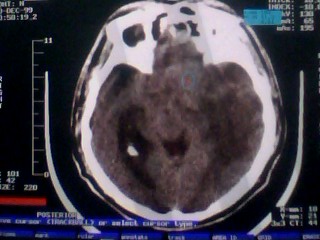

以下是引用随光逐影在2010-1-7 14:49:00的发言:[br]1)结合病史,考虑多发性脑转移瘤可能性大;建议行ct增强扫描检查。2)大脑镰下疝。3)脑积水。